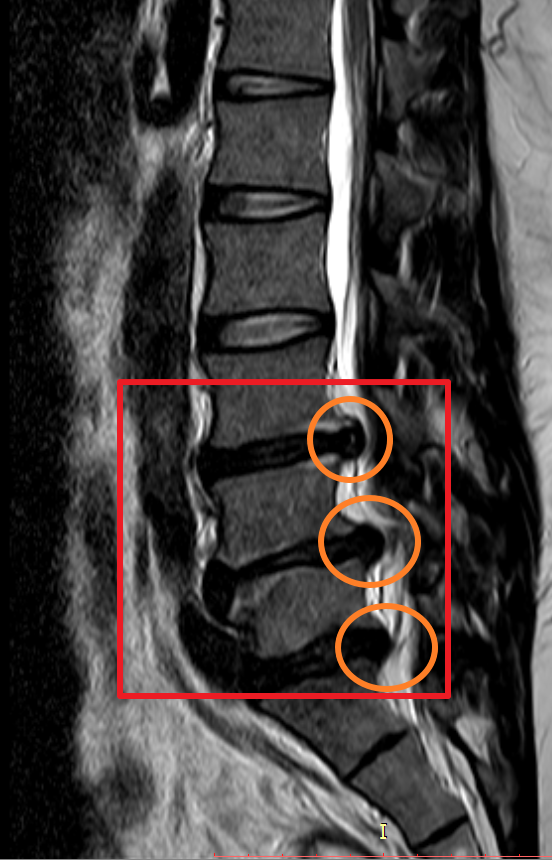

하지만 몸 관리를 꾸준히 잘하지 못하였고 4년 뒤 다시 허리디스크 상태가 악화하여 두 번째 MRI를 찍어보니 이전에 발병한 위치와 다른 곳에서 신경을 누르고 시작하였고 이전에 최초 발병한 허리디스크(첫 번째 동그라미)는 좀 나아졌으나 다른 곳에서(두 번째, 세 번째 동그라미) 또 문제가 생겼더군요.

마지막 허리디스크 MRI는 2020년에 촬영했습니다. 마찬가지로 사진을 보시면 최초 발병한 허리디스크 첫 번째 동그라미는 흡수가 된 게 눈에 보일 정도였으나 4년뒤엔 두 번째 동그라미와 세 번째 동그라미 디스크가 많이 튀어나와 신경을 누르고 있는 게 보입니다.

마지막으로 제가 촬영했었던 MRI 촬영 이미지를 첨부해 볼까 합니다. 이미지 순서대로 2014년, 2018년, 2020년 촬영했던 MRI 사진입니다. MRI 촬영 당시 허리디스크 상태가 좋지 않은 상황에서만 세 차례 찍었던 것이기에 이점도 고려해서 참고하시면 좋을 듯합니다.

이미지를 보시면 빨간색 네모 칸에 하얀색 기다란 세로 라인이 신경이 지나가는 부분이며 가장 바깥쪽 두꺼운 흰색 부분은 배 쪽의 지방입니다.

2018년 첫번째 허리 디스크가 첫번째 디스크가 여전히 눌려져 있으며 추가로 두번쨰 디스크가 신경을 많이 누르고 있으며 세번째 디스크는 조금씩 나오는 상황.

2020년 첫번째, 두번째 터졌던 허리디스크가 많이 흡수되어 신경을 누르고 있는 디스크 압박이 많이 좋아졌으나 세번째 허리디스크가 터진 곳이 심해진 상황.